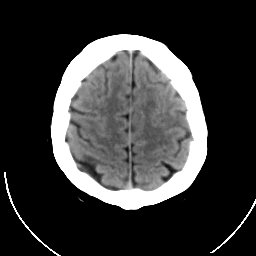

CT Study #1 -- Slice #19